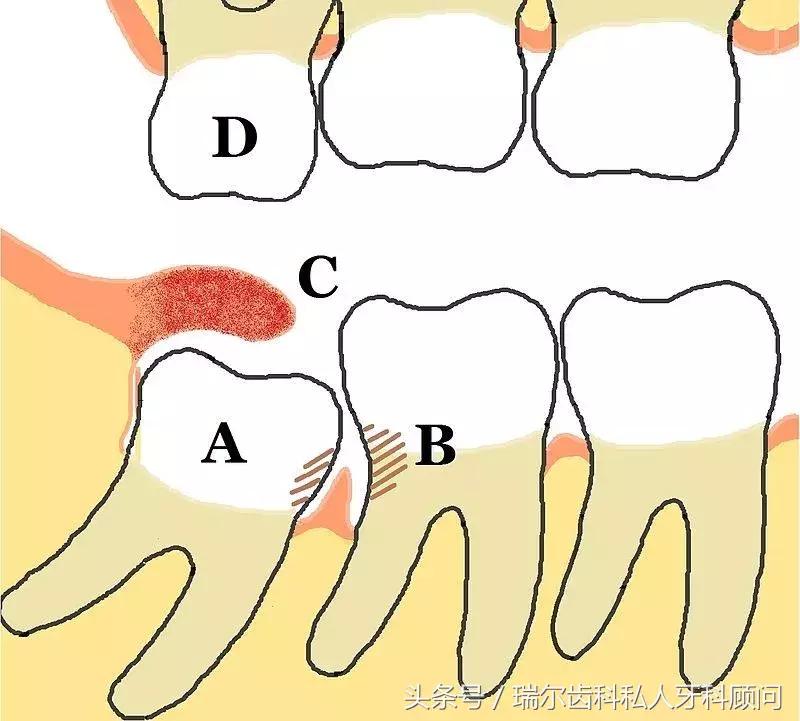

智齿冠周炎反复发作。当智齿萌出受阻,牙龈组织在智齿周围形成牙龈袋(下图红肿的位置),细菌在此繁殖生长,一旦出现创伤或免疫力受损,炎症便会找上门,牙龈肿胀疼痛;若不及时治疗,感染继续扩散,将会出现面部肿胀、发烧、张不开嘴等症状。

↑ 示意图

智齿会毁了你的第二磨牙。那些靠着第二磨牙(与智齿相邻的牙齿)牙根生长的智齿,会在萌出时产生作用于第二磨牙牙根表面的破骨细胞,使牙根逐渐吸收,破坏牙神经,引起疼痛,甚至脱落。此外,智齿阻生或错位,会导致与第二磨牙形成卫生死角,不易清洁,久而久之引发第二磨牙龋齿。